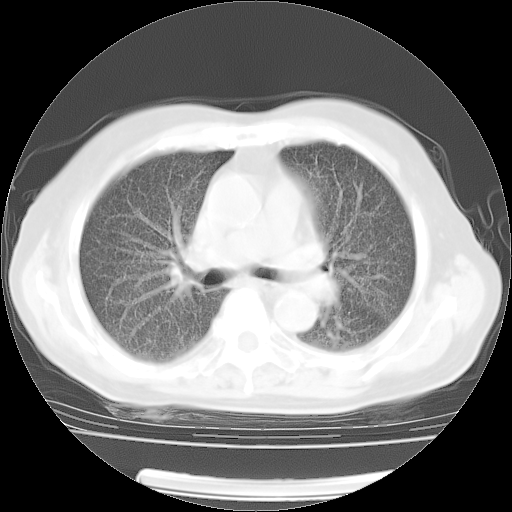

4月14日肺部CT

27.JPG

28.JPG

29.JPG

30.JPG